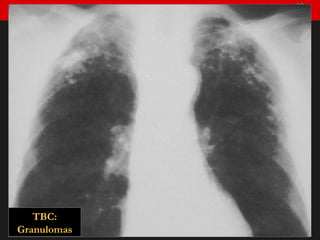

TBC: Granulomas

Infección pulmonar tuberculosa Primoinfección. Complejo primario Infiltrado periférico (neumonía) Linfangitis Adenopatías mediastínicas 1. Granuloma 2. Fibrosis 3. Calcificación 1.  2.  3.  Resolución espontánea. Cicatrización

Infección pulmonar tuberculosa Reinfección: Formas de presentación Neumonía cavitada Linfadenitis Pleuritis Diseminación bronquial Diseminación hematógena (Miliar) Fistulizaciones Afectación de otras vísceras

Infección pulmonar tuberculosaPrimoinfección. Complejo primario Infiltrado periférico (neumonía) Linfangitis Adenopatías mediastínicas 1. Granuloma 2. Fibrosis 3. Calcificación 1. 2. 3. Resolución espontánea. Cicatrización

Infección pulmonar tuberculosaReinfección: Formas de presentación Neumonía cavitada Linfadenitis Pleuritis Diseminación bronquial Diseminación hematógena (Miliar) Fistulizaciones Afectación de otras vísceras